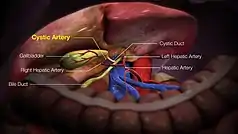

| Cystic artery | |

The cystic artery branches from the right hepatic artery. | |

| Source | Right hepatic artery |

| Branches | Superior branch Deep branch |

| Supplies | Gall bladder and cystic duct |

The cystic artery (also known as bachelor artery) is (usually) a branch of the right hepatic artery that provides arterial supply to the gallbladder and contributes arterial supply to the extrahepatic bile ducts.

The cystic artery arises from the right hepatic artery in about 80% of cases.[1]

It usually passes posterior to the common hepatic duct within the cystohepatic triangle. Within the triangle, it is usually superior to the cystic duct (if it does not pass superior to the cystic duct, it may be situated outside the triangle).[1]

Upon reaching the superior aspect of the neck of the gallbladder, it splits into superficial and deep branches. These branches then form an anastomotic network over the surface of the body and fundus of the gallbladder.[1]

- The superficial branch (or anterior branch) passes subserously over the left aspect of the gallbladder.

- The deep branch (or posterior branch) runs between the gallbladder and gallbladder fossa, terminating at the peritoneum attached to the liver surface.